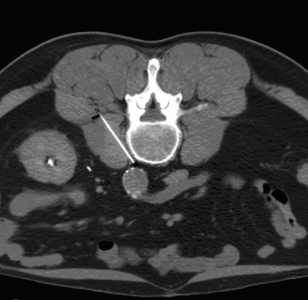

Die durchleuchtungs- und computertomographie-gesteuerte periradikuläre, epidurale und intradiskale Schmerztherapie (PRT) wird im Institut für Radiologie der Augusta-Kranken-Anstalt häufig zur Behandlung von Bandscheibenvorfällen, entzündlichen und degenerativen Bandscheibenveränderungen an den Segmenten der Lenden- (Abb. Links) und Halswirbelsäule (Abb. Mitte Links) , seltener auch an der Brustwirbelsäule eingesetzt. Unter bildgebender Kontrolle wird in örtlicher Betäubung eine dünne Hohlnadel an die Nervenwurzeln oder in die Bandscheibe im erkrankten Wirbelsäulenbereich vorgeschoben. Durch die Kontrolle in der CT wird eine millimetergenaue Platzierung der Nadel erlaubt. Durch eine simultane Kontrolle mittels Durchleuchtung (C-Bogen am CT) gelingen auch schwierige Positionierungen z.B. im Segment L5/S1 (Abb. Mitte Rechts). Die korrekte Nadellage wird jeweils durch Gabe von 0,5 ml Kontrastmittel überprüft, wobei auf eine Anfärbung der epiduralen Räume (bzw. bei intradiskaler Therapie auf eine Kontrastierung des Gallertkernes der Bandscheibe) Wert gelegt wird (Abb. Rechts).

Der lumbale Sympathikus besteht aus drei bis vier Nervenganglienpaaren, die an der Vorderkante der Wirbelkörper rechts und links der großen Gefäße und des beiderseitigen Musculus psoas im Fettgewebe liegen. Die Rami communicantes verbinden die Ganglien strickleiterartig sowohl nach kranio-kaudal als auch von links nach rechts. Eine weitere Umschaltung erfolgt über die Rami albi, die durch die Neuroforamina neben den Segmentnerven zum Duralsack verlaufen und dann im Rückenmark weitergeleitet werden. Bei umschriebenen peripheren arteriellen Verschlüssen kann bei der Sympathikolyse mit einer hohen Erfolgsrate (ca. 75%) gerechnet werden. Der beste Effekt lässt sich in Kombination mit einem intensiven Gehtraining erzielen. Als gute Indikationen zur lumbalen Sympathikolyse zählen Verschlüsse der Unterschenkel- und Fußarterien auch bei kombinierten Oberschenkelverschlüssen. Trophische periphere Ulcera sind durch die lumbale Sympathektomie ebenso wie Nekrosen der Zehen zu behandeln. Bei ca. 45 Prozent der Patienten mit Stadium IV können sich die Nekrosen vollständig zurückbilden. Patienten mit Diabetes mellitus zeigen in der Regel ein schlechteres Ansprechen. Die lumbale Sympathikolyse ist durch die CT-Kontrolle heute zu einer Standard-therapie bei der Behandlung von peripheren arteriellen Durchblutungsstörungen geworden. Die beste Indikation ist im Stadium III nach Fontaine gegeben, aber auch im Stadium IIb kann bei schlechter Ausstrombahn in Kombination mit gefäßchirurgischen Eingriffen oder einer Angioplastie eine Indikation vorliegen. Die Nebenwirkungen sind wegen der hohen Präzision der CT-Steuerung gering. Da die Behandlung unter Lokalanästhesie durchgeführt wird, kann in vielen Fällen eine ambulante Therapie erfolgen. In Bauchlage werden nach Gabe von 1 ml Kontrastmittel pro Kilogramm Körpergewicht die Ureteren kontrastreich in der Ausscheidungsphase dargestellt. Nach Lokalisation der sympathischen Ganglien durch eine Spiral-CT des Mittel- und Unterbauches werden die Einstichstellen an der Haut bestimmt und markiert. Nach Lokalanästhesie der Haut und der autochthonen Rückenmuskulatur wird eine 22 G Shiba-Nadel durch den Musculus psoas zu den jeweiligen Ganglien unter lokaler Anästhesie vorgeschoben (Abbildung). Etwa 0,5 ml Kontrastmittel wird zur Prüfung der Verteilung am Sympathikus injiziert. Zur Ausschaltung des Sympathikus sind bei exakter Positionierung der Nadelspitze ca. 5 bis 10 ml 95%igen Alkohols erforderlich.